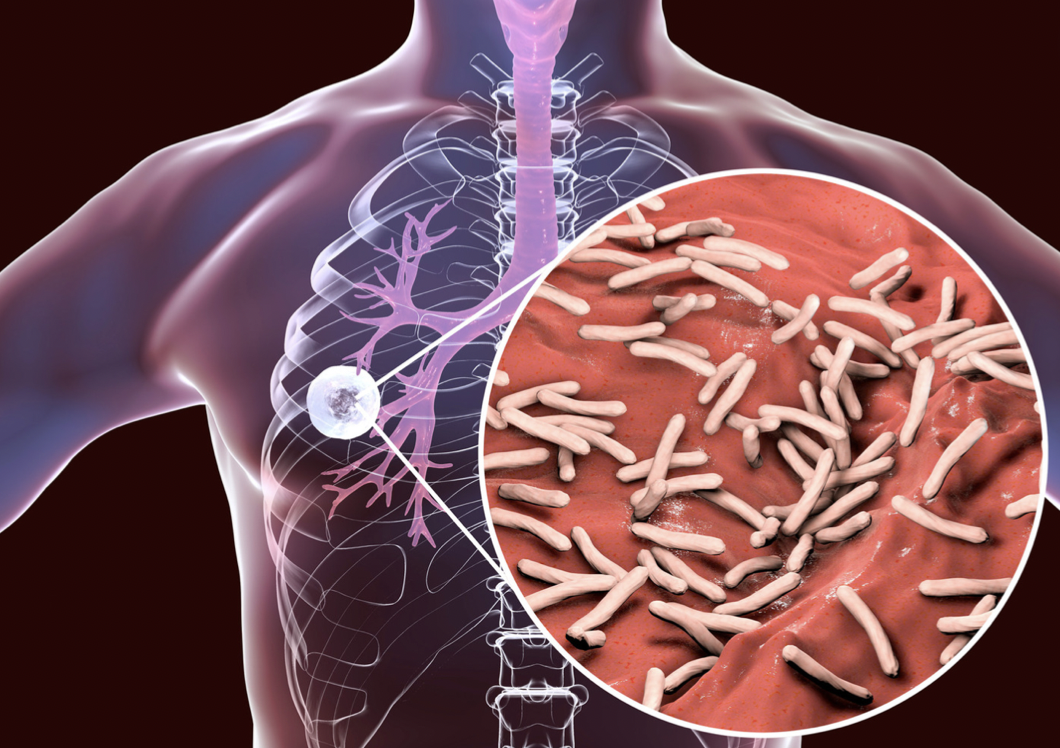

TAG: infeksi paru

infeksi paru

"Infeksi Paru"